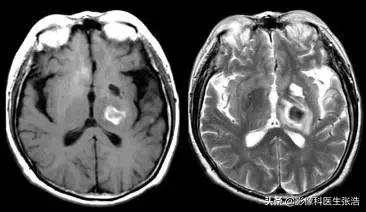

(2)急性期:一般为1-3天。

该期红细胞内为去氧血红蛋白,它有4个不成对电子,具有顺磁性,局部场强不均,T1加权像仍成稍低信号。

脑出血急性期